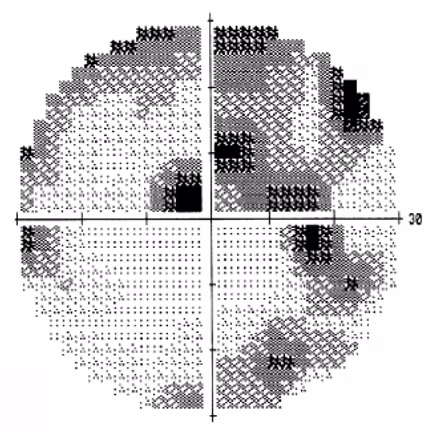

Professionele diagnose en behandeling van glaucoom met moderne apparatuur.